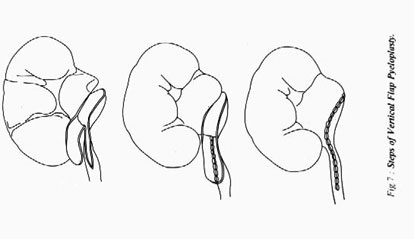

2. A függőleges szárny pyeloplasty

Fig.7 Steps műanyagok lohanochnomochetochnikovogo függőleges szárny szegmens medencét.